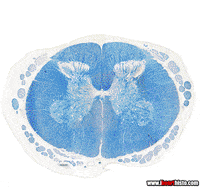

Zintifa GIFCartoon gif. Jake from Adventure Time Looks up with big sparkly eyes like he’s begging. His pleading frown changes to a wrinkly smile and he places his paws on his cheeks in excitement.Sad Dexters Laboratory GIF by Cartoon NetworkCartoon gif. Jake the dog from Adventure Time on Cartoon Network blinks its large white eyes, raising its skinny yellow arms into a shrug.regular show pops GIFadventure time fist bump GIFcartoon network hug GIFcartoon network 90s GIFnervous system anatomy GIFHappy Teen Titans GIF by DCRegular Show Mordecai GIF by Cartoon NetworkMess Arreglar GIF by Cartoon Network EMEA